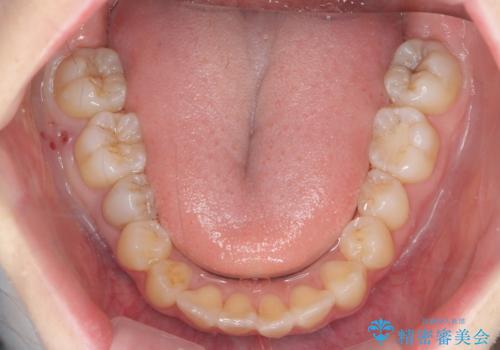

下の八重歯 歯を抜かずに インビザライン治療

- 歯並びのがたつきを主訴に来院。

抜歯してワイヤー矯正という選択肢も提案しましたが、マウスピース矯正で、歯を抜かずに並べてほしいとのことでした。

スペースを確保するために、歯をわずかに削る処置、奥歯を後ろに下げる処置(インプラント矯正)を行っています。